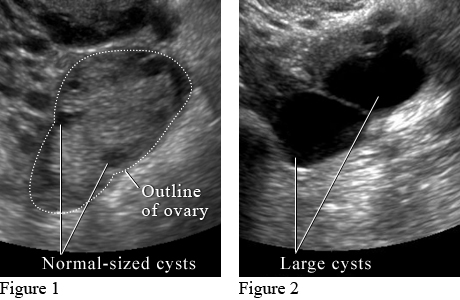

Ultrasound of Ovarian CystsImage courtesy of Intermountain Medical Imaging, Boise,

Idaho. Figure 1 shows small normal-sized cysts. Figure 2

shows large cysts that affect the ovary and may cause